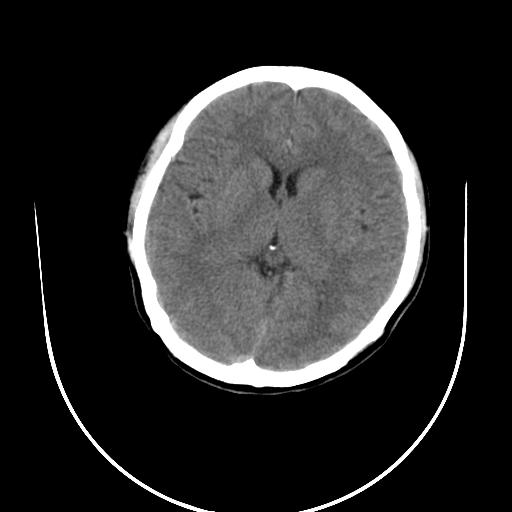

标题: CT10010:女/24岁,癫痫一周,发作时间不固定. [打印本页]

标题: CT10010:女/24岁,癫痫一周,发作时间不固定.

右侧额叶正常吗?

右额叶镰旁饱满.

右侧外侧沟?中央沟?可能有问题,不知以前有没有癫痫过,最好是增强下,排除局部血管畸形等病变

倒数第6幅图中线结构有点偏,而侧脑室额角未见异常,可结合增强扫描。